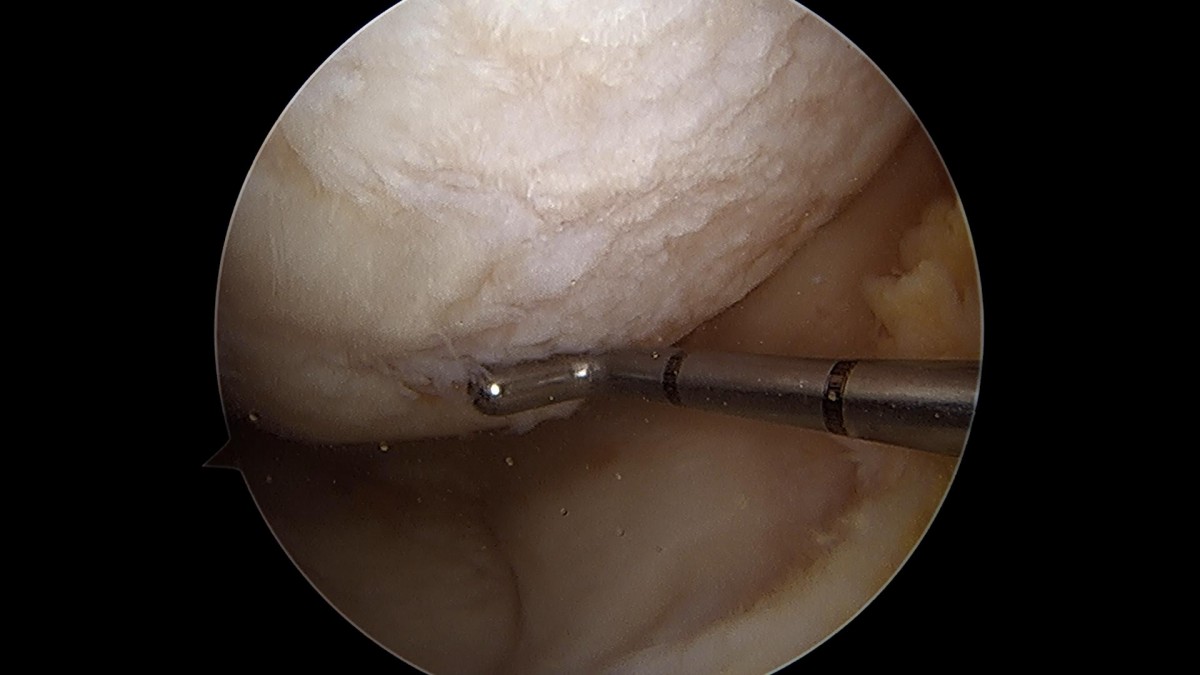

배우한원장님 무릎 반월상 연골판 파열 수술 (782)염광O 환자

작성자 최고관리자 댓글 0건 조회 1,058회 작성일 22-02-23 12:40